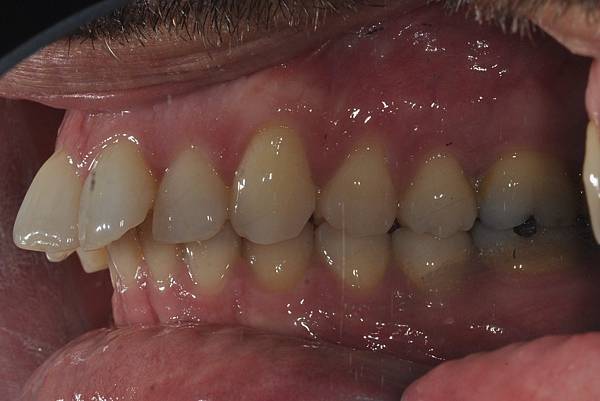

台灣的牙科醫療品質, 連外國人都說讚!此案例為深咬合併二級咬合 林醫師藉由正中上顎骨釘(HPPG technique)做上顎全齒列後移改善暴牙 讓本來五官就相當立體的艾先生,笑起來更燦爛了! 治療前/治療後-以上案例由林昇進醫師提供 分享到